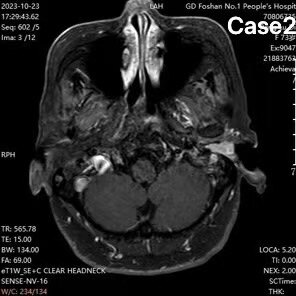

耳痛最常見的原因是外耳道炎,但也不全是,這例曾經(jīng)耳痛一年,被以為是外耳道炎,后來又診斷為三叉神經(jīng)痛,最后在我們科診斷為外耳道癌,行了根治手術(shù),疼痛終于解決。資料顯示,外耳道癌的年發(fā)病率約為百萬分之一,按這樣說,一個千萬人口的大城市,每年發(fā)病10個左右。但有時有些累積下來的病例,一年發(fā)現(xiàn)幾十個也不足為奇。